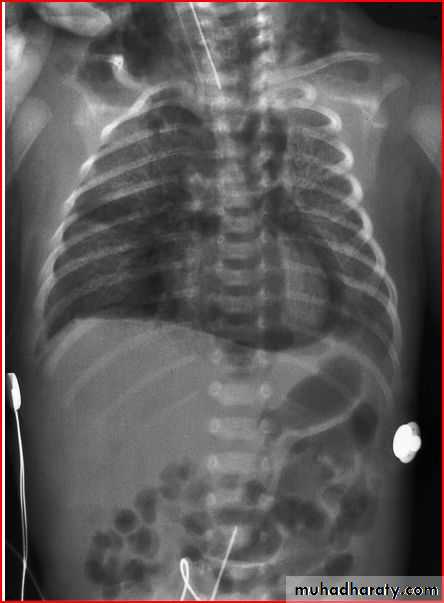

3 month infant presented with cough & dyspnea

Xray shows hyperinflated chest (depresed diaphragm , > 6 ribsMay be bronchiolitis

Hyperinflated chest